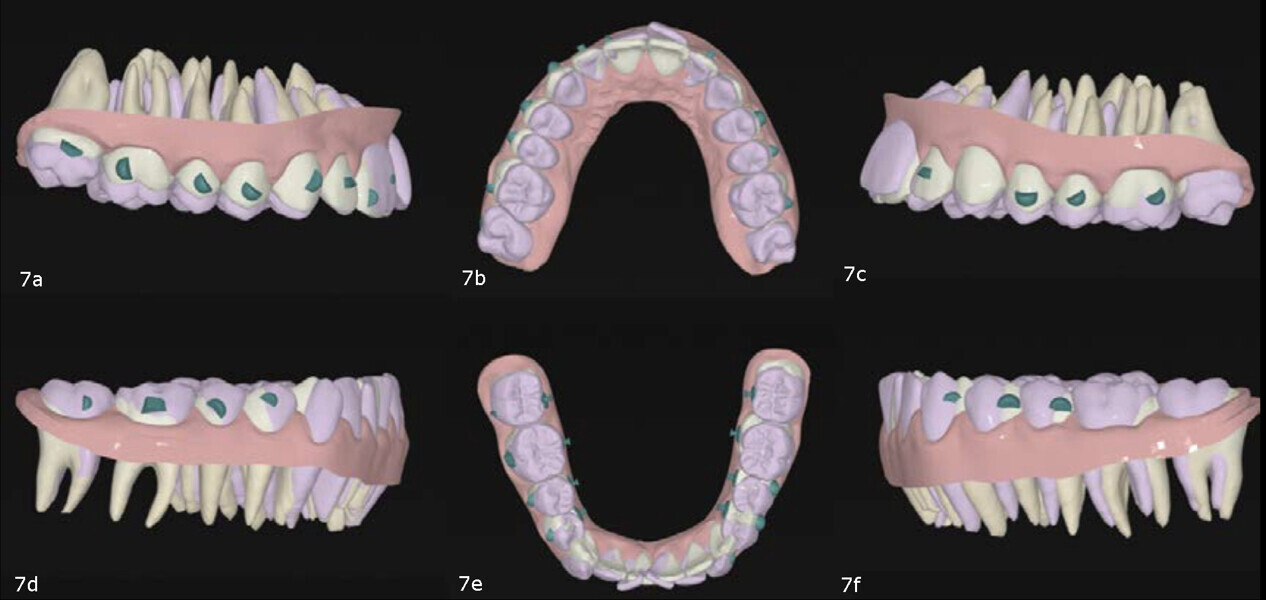

Using the system’s treatment planning software, we simulated (1) alignment and levelling of both arches (without incisor protrusion), (2) maxillary dentoalveolar expansion, (3) posterior intrusion in both the maxilla and mandible, (4) mandibular midline correction and, ultimately, (5) mandibular auto-rotation. To resolve the mandibular crowding without further proclining the teeth, we incorporated posterior IPR (Fig. 7).

In the 3D digital treatment set-up, both maxillary and mandibular arch forms were improved by applying positive torque to the posterior segments, facilitating proper alignment and levelling. Specific planned movements included proclination of the maxillary incisors, and retraction and intrusion of the mandibular incisors. IPR in the mandibular arch was planned in order to relieve crowding without further proclination.